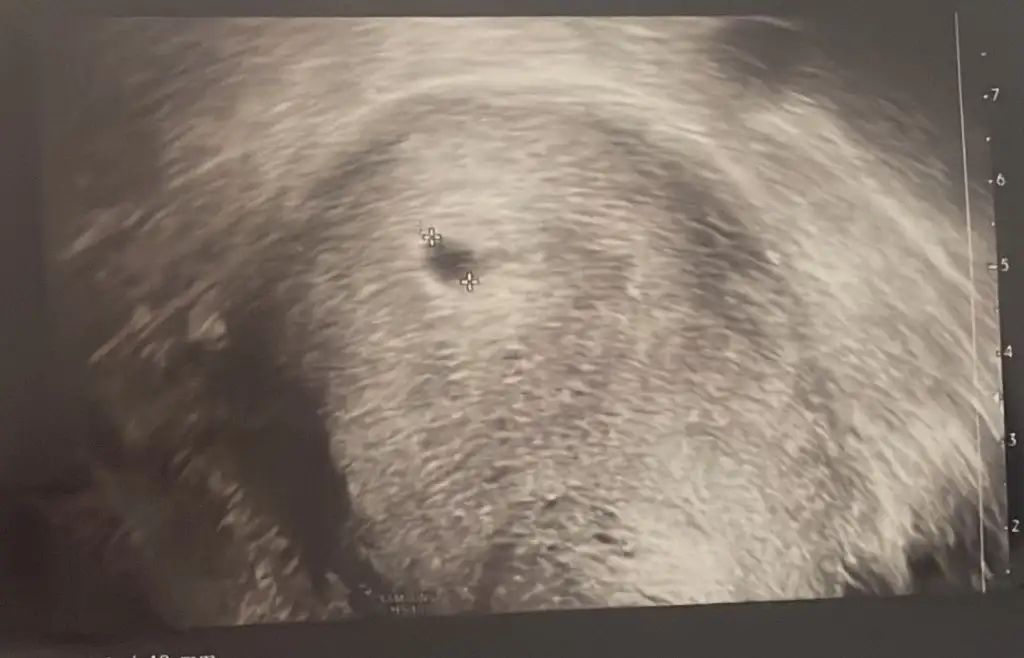

Kızlar 5.haftada keseyi görenlere bi sorum var. İçinde yolk sac nasıldı kesenizin içinde baya belli miydi nokta gibi miydi